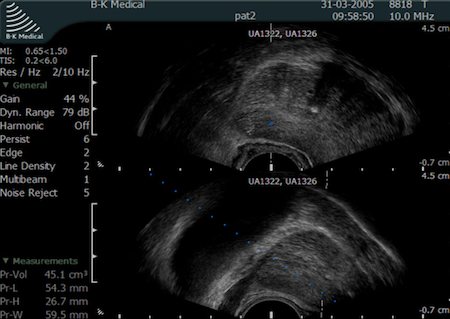

Biopsja gruczołu krokowego